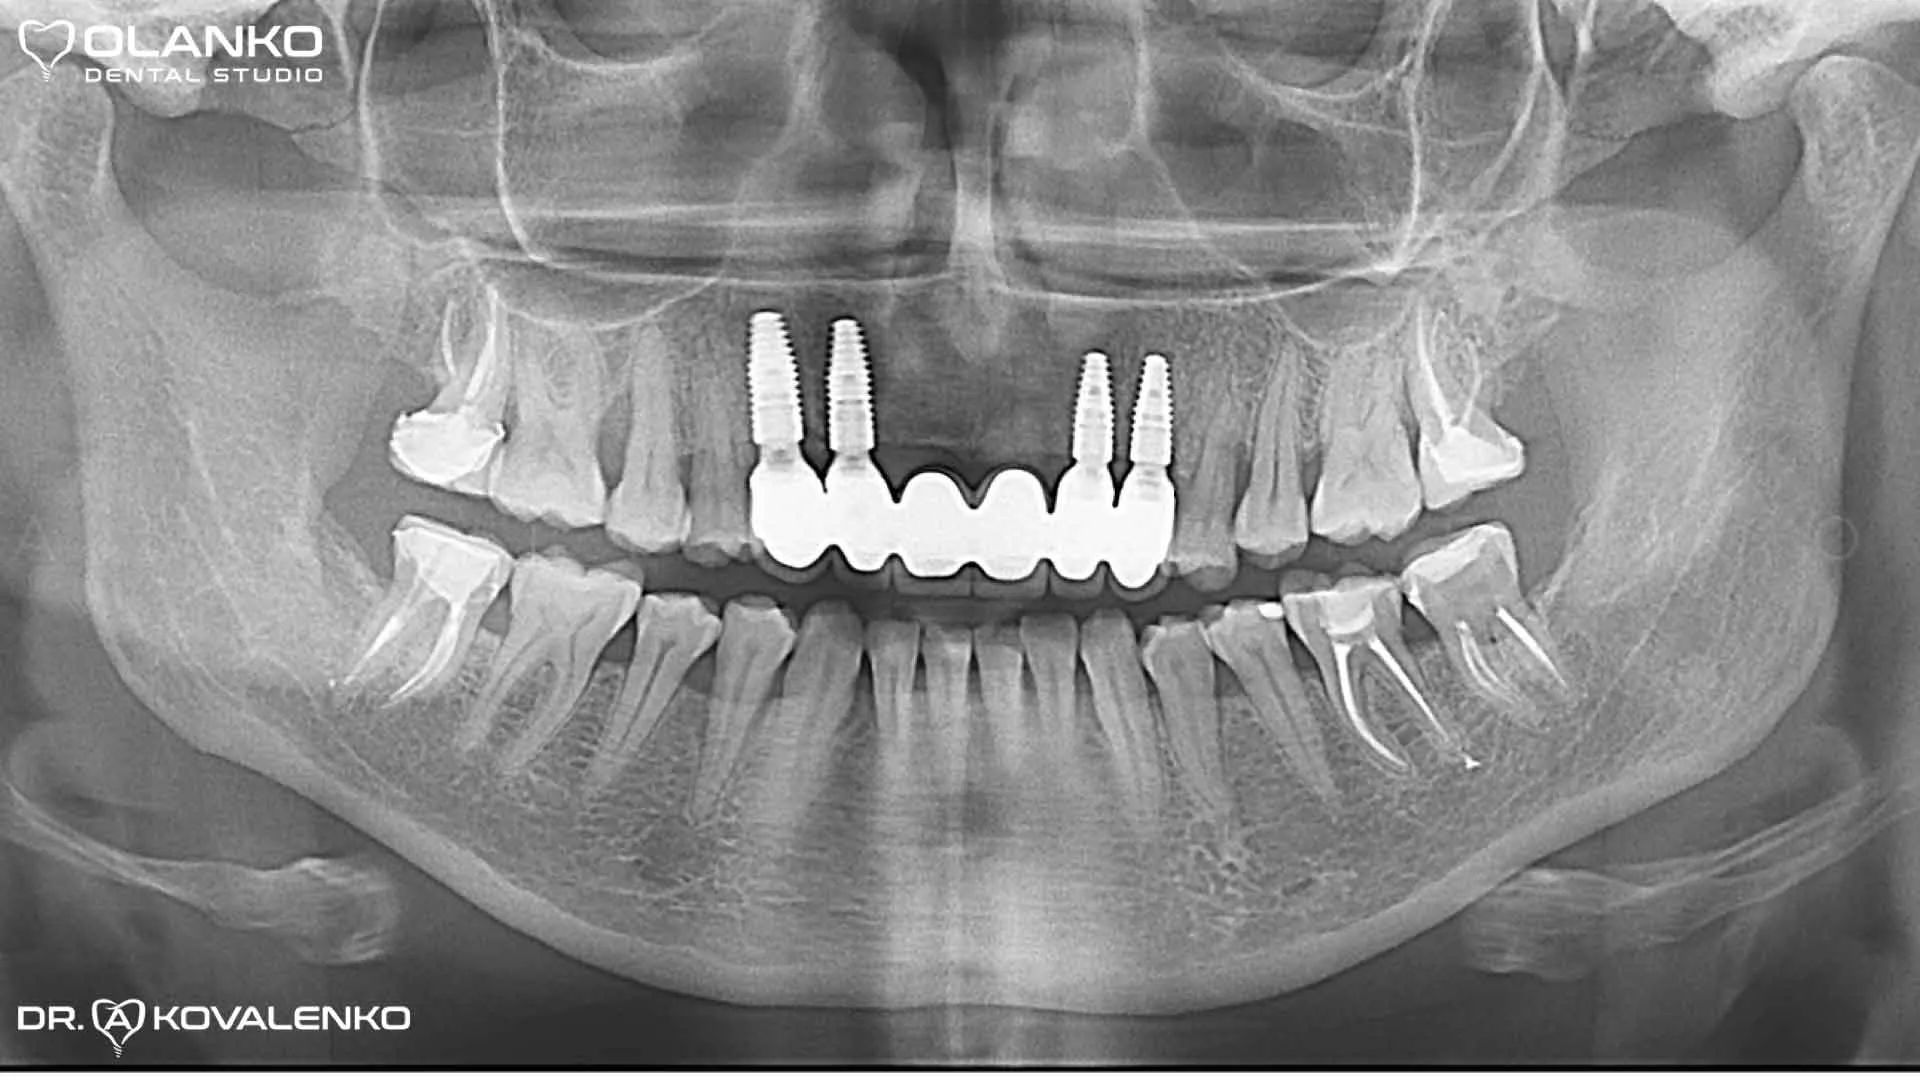

Контрольный панорамный рентген снимок после окончания протезирования на имплантатах

Клинический случай 8 имплантация зубов